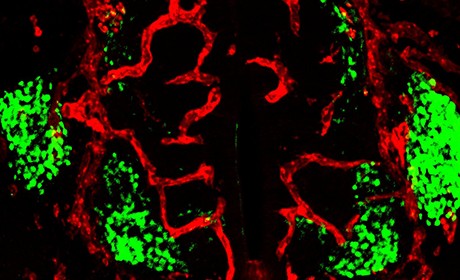

Confocal microscopy image showing a spinal cord section of a mouse embryo (embryonic day 11.5). The blood vessels (red) grow around the motor neurons (green).

Heidelberg Neuroscientists have identified a critical regulator for blood vessel growth in the developing embryonic spinal cord. The research group under the direction of Dr Carmen Ruiz de Almodóvar of the Heidelberg University Biochemistry Center discovered that special nerve cells known as motor neurons control this process. This new insight into the nature of the interrelationship between the nervous system and the vascular system will help in understanding diseases of the central nervous system. These The nerve cells of the central nervous system (CNS), which is composed of the spinal cord, the brain, and the retina, must be supplied with sufficient oxygen and nutrients through the blood vessel system during development and their subsequent function. 'Moreover, there is an active bidirectional communication between the nerve cells and the blood vessels to ensure the proper development and maintenance of an organ as complex as the brain," reports Carmen Ruiz de Almodóvar. Research of the last decade revealed that the CNS and the vascular system share many molecular mechanisms and signaling pathways, which is also known as neurovascular link. However, still most of these molecular mechanisms remain poorly understood.